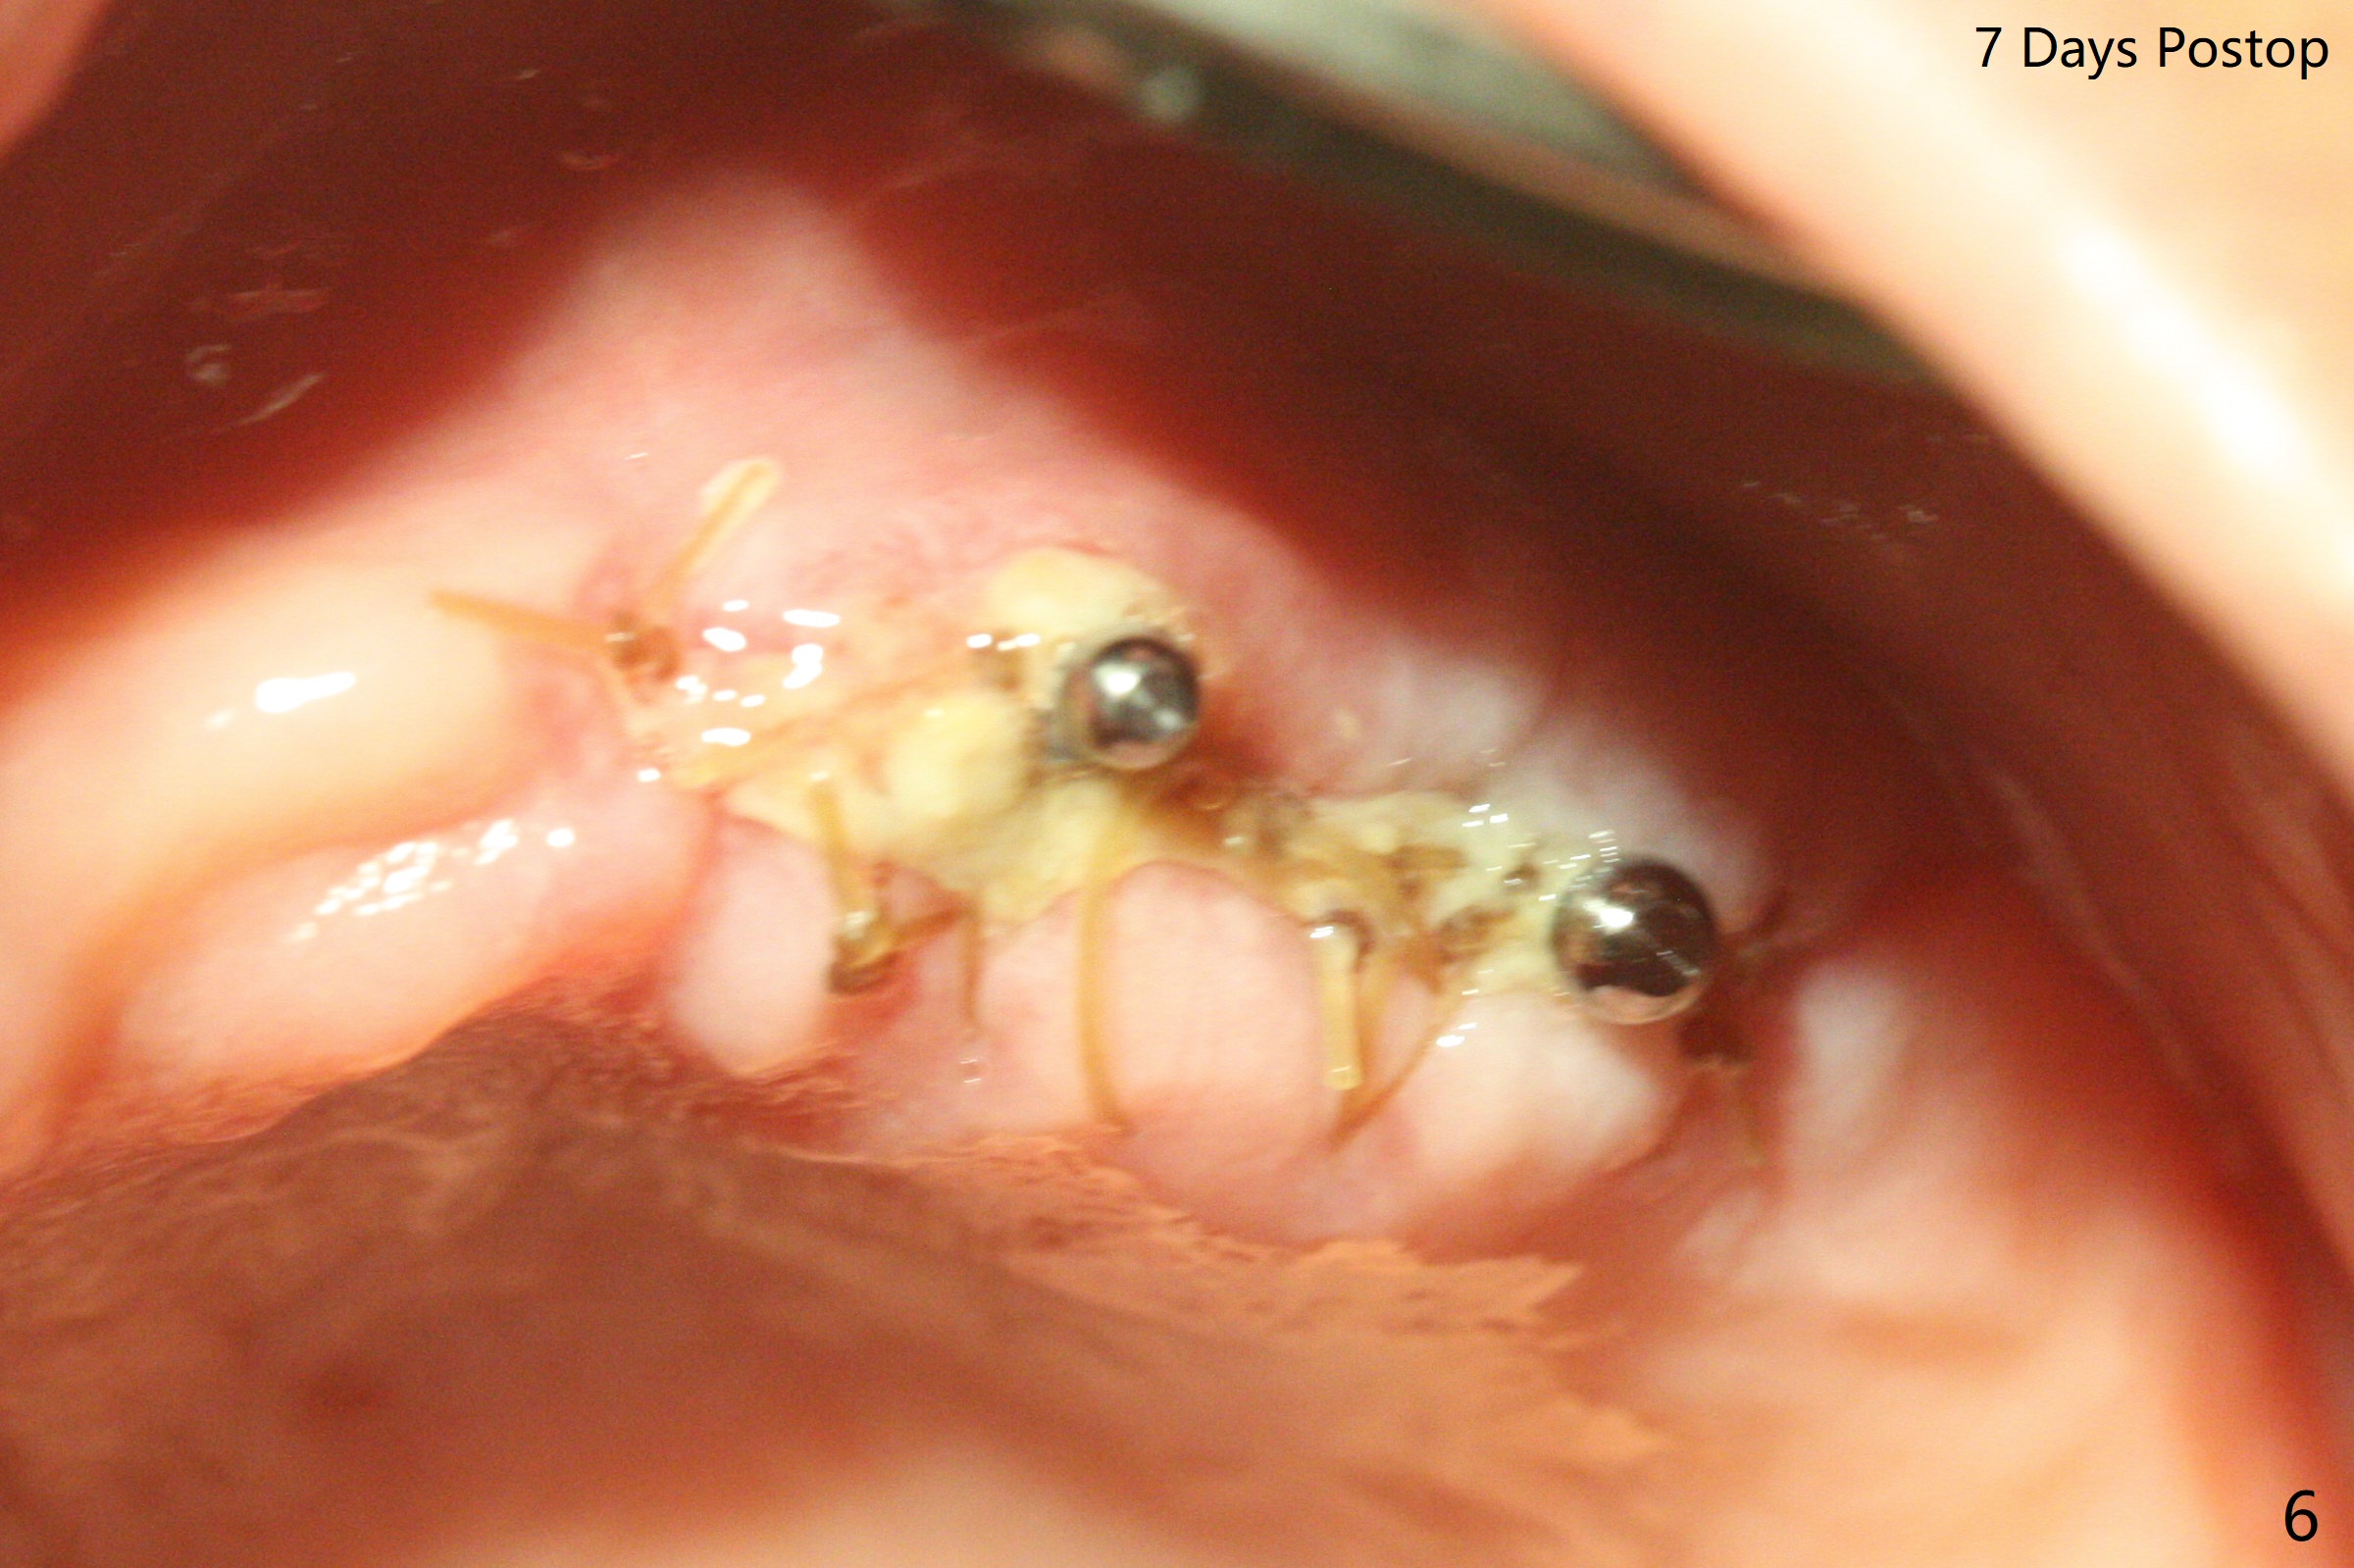

63岁女有上下活动局部假牙,由于右下侧切牙折裂(26号牙)就诊,保守处理(重新粘固)。虽然病人满意上颌义齿,而且非常害怕牙科治疗,并不想多花钱,但是对左上两个植牙固位假牙有兴趣。原计划在尖牙和第二双尖牙(11和13号牙),CT检查表明11号牙处牙槽骨太窄,所以改为12和13处种植(3.5乘10,4乘10毫米)。12号牙处牙槽嵴截除后,颊舌侧宽度仍不够,钻洞直径2毫米(图一),似乎不得不用一体式带球帽植体(1-piece implant with ball abutment),2.5乘10(4)毫米(图二至四;N: 鼻腔,S: 上颌窦),并且在它周围植骨(图三,四 *)。在假牙相对位置创造空间后,做软衬里(图五)。对于恐惧病人,尽管带球帽植体精确度要求不高,导板还是必要的。一周以后病人十分感激,因为没有痛(图六)。术后一个月她很高兴告诉我们自从植牙后,托牙下面不容易积累食物了。